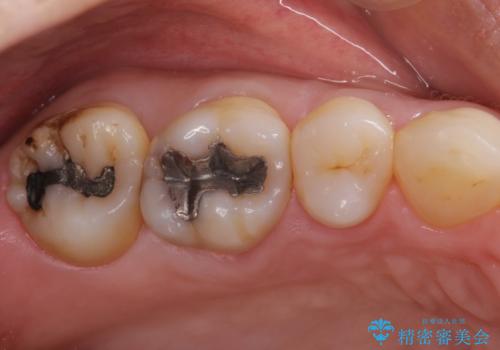

むし歯の治療。ゴールドインレーによる修復

- 定期健診にてむし歯を認めたためゴールドインレーにて治療を行いました。

拡大鏡で常に口腔内を診察しているため、小さなむし歯も見逃さずに治療を行っています。